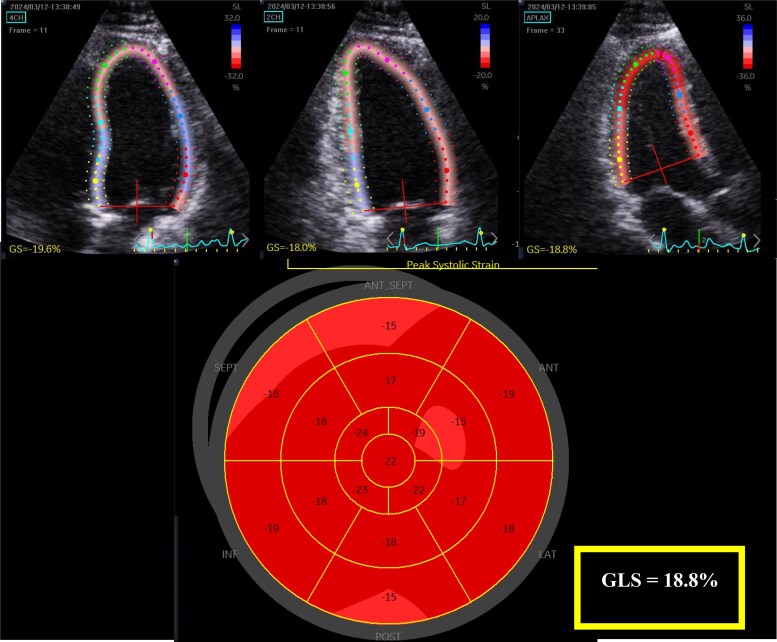

Methods and results: Fifty-six AFD patients were age- and sex-matched to 56 healthy controls. LV global longitudinal strain (GLS) and LA reservoir strain (LASR) were significantly lower in male (GLS: 19.38[3.21] vs. 17.8[7.0], P = 0.009; LASR: 38.07 ± 6.67 vs. 31.12 ± 6.76, P = 0.003) and female (GLS: 20.58 ± 1.63 vs. 19.29 ± 1.67, P = 0.003; LASR: 38.77 ± 7.43 vs. 33.13 ± 6.06, P < 0.001) AFD patients compared with controls. Reduced strain parameters were also seen in female AFD patients with normal wall thickness (GLS: 20.88 ± 1.74 vs. 19.72 ± 1.53, P = 0.037; LASR: 40.09 ± 7.15 vs. 34.79 ± 6.20, P = 0.004). 53/56 AFD patients had a median follow-up of 43[81] months; 11/53 experienced an adverse cardiovascular event (i.e. cardiac death, myocardial infarction, arrhythmias, stroke. and heart failure). LV wall thickness, LAVImax, and LV GLS displayed good sensitivity and specificity for adverse cardiac events. A prognostic risk decision tree comprising of these parameters demonstrated good predictive value for adverse events (AUC = 0.910).

Conclusion: We demonstrate differences in LV and LA echocardiographic parameters in AFD patients compared with healthy controls, including female AFD patients with normal LV wall thickness. A prognostic risk decision tree stratified AFD patients into three groups with the highest risk group demonstrating more AFD-related adverse events.